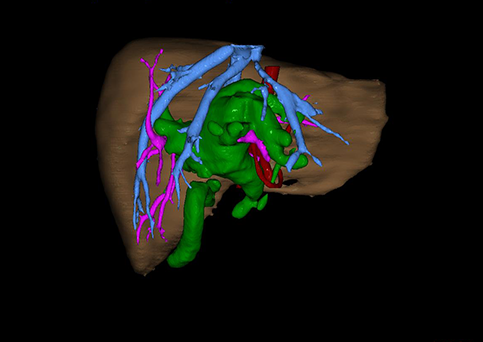

10、三维重建虚拟肝脏、胆道显像技术

三维虚拟肝脏技术是在二维影像学资料如CT等图像的基础上,通过三维重组软件和工具,比如青岛大学附属医院与海信医疗集团联合自主研发的海信计算机辅助手术系统(Hisense Computer Assisted Surgery,Hisense CAS),目前已投入临床并指导实际应用,利用该类系统对二维影像学的数据资料进行三维立体分析,重组形成立体的、有空间结构的、虚拟的肝脏三维图像。这项技术较传统的二维平面成像技术,有着明显的优势,3D虚拟肝脏技术可以构造出一个虚拟的、可视化的肝脏模型。通过对这种模型的观察,可以很容易地分辨出肝脏器官的组织结构、解剖特点,直观研究肝外胆总管的形态差异,明确肝内胆管的形态、走形、是否合并扩张、狭窄及结石,胰胆管合流的形态及共同通道内是否有狭窄、扩张和结石等病变情况,预先规划处理可能合并存在的肝内胆管扩张、狭窄或其他复杂胆道畸形,清晰地显示肝内脉管系统,包括门静脉、肝动脉及肝静脉的走行、分支,并可多角度、全方位观察病变胆道与其周围重要血管尤其是伴行的门静脉之间的解剖关系,大大提高了外科医师在术前对肝脏内部各管道结构及其变异判断的精确性和可靠性,精准地对病变进行判断和评估,还可根据患者自身的病变特点,制定出合理、个体化的手术方案,最大限度地降低术中和术后并发症发生率,并术中导航实时指导手术,提高手术的精准性和成功率。

图10:先天性胆管扩张症囊肿型三维重建虚拟肝脏、胆道显像

a 图为术前二维CT扫描图像,箭头所示为肝内胆管扩张;b 图为CT经多平面重组技术(MPR)图像后处理所得的重建图像,可显示胆总管明显扩张合并肝内胆管扩张;c 图为MRCP显示胆总管呈囊柱状扩张,直径>1 0 cm,伴肝内胆管扩张;d 图示Hisense CAS三维重建清晰显示肝脏、胆道系统及其与门静脉、肝动脉、肝静脉等之间的空间解剖关系;e 图示Hisense CAS可从任意角度以不同脏器组合显示,明确胆道系统与其伴行的门静脉系统的空间解剖关系;f 图示胆道系统立体形态及与肝脏整体的空间关系,箭头处显示肝内胆管狭窄部位发生于左右肝管汇入肝总管处。术前规划需行肝内胆管扩大成形术。